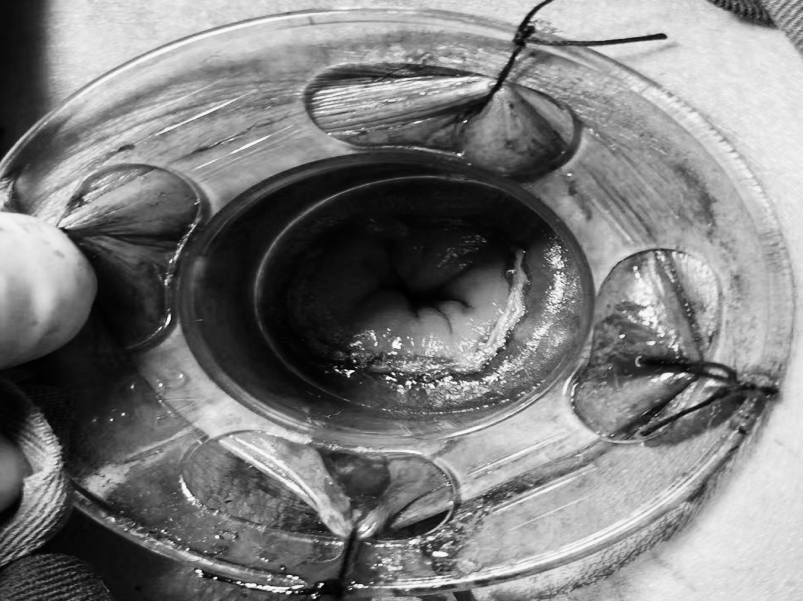

直肠脱垂是指直肠壁的一部分或全层向下移位,最终可能脱出肛门外的疾病。它并非肿瘤,但在老年人、多次分娩的女性、长期便秘或慢性咳嗽等腹压增高人群中较为常见。 【关键诱因与表现】 直肠脱垂主要因盆底肌肉、韧带等支撑结构松弛,加之长期腹压增高(如用力排便、慢性咳嗽、排尿困难)诱发。患者常感肛门坠胀或异物感,典型表现为排便或久站后有柔软肿物自肛门脱出,初期或可自行缩回,后期常需手法复位,并可伴排便困难、不尽感、肛门黏液或血性分泌物、潮湿瘙痒,严重者可能出现排便控制困难。 【治疗选择因人而异】 保守治疗(轻度或早期): 核心是消除诱因: 积极改善便秘(高纤维饮食、充足饮水、必要时遵医嘱用药)、控制咳嗽、解决排尿困难。 生活方式调整: 避免久蹲、久站、负重及用力排便。 盆底肌锻炼(凯格尔运动): 坚持锻炼有助于增强盆底支撑力。 及时复位: 轻柔地将脱出部分复位,防止卡住肿胀。 手术治疗(中重度或保守无效): 当脱垂严重影响生活、难以复位、反复出血或出现排便失禁等情况时,医生会评估手术的必要性。 手术目标是修复薄弱的支撑结构,将直肠固定在正常位置。有多种手术方式(包括微创方法),医生会根据个体情况选择最合适的方案。 【重在预防与管理】 预防的关键在于减少腹压增高因素: 1.保持大便通畅,避免用力排便。 2.积极治疗慢性咳嗽、前列腺增生等导致腹压增高的疾病。 3.坚持规律进行盆底肌锻炼。 4.维持健康体重,避免长期重体力劳动。 直肠脱垂虽然带来不适,但通过及时就医、明确诊断并接受规范治疗(包括生活方式调整和必要的医疗干预),多数患者的症状可以得到有效控制,生活质量显著提升。如有相关疑虑,建议咨询肛肠专科医生。 注:部分图片来源于网络,如有侵权,请联系删除。 贵州航天医院普外科专家简介 高大勇 普外科(肛肠外科)学科带头人、名誉主任,主任医师、教授 临床擅长:对中西医结合诊治肛肠学科各种常见病、多发病及疑难杂症等具有丰富的临床经验。 原遵义市第一人民医院(遵义医科大学第三附属医院)、遵义市中医院肛肠科主任。中华中医药学会肛肠分会常委,全国中医肛肠学科名专家,中国健康促进与教育协会肛肠分会常委,中国康复医学会肛肠疾病康复专业委员会常委,中国民间中医医药研究开发协会肛肠分会副秘书长,中国医师协会中西医结合肛肠医师专业委员会常委,国家二级心理咨询师,贵州省第一批中医名医工作指导老师,遵义市名中医,遵义市肛肠学会会长,遵义市肛肠质控中心名誉主任,遵义市中西医结合学会名誉会长,遵义市健康科普专家,原贵州省中西医结合学会肛肠分会副主任委员、贵州省中医肛肠质控中心副主任、遵义市医学会医疗鉴定委员会专家、遵义市卫生系列高评委。发表论文30余篇,主编和参编医学著作5本,主持省级科研课题2项、市级科研课题2项、院级科研课题1项。 梁 跃 中共党员,普外科党支部书记、主任,主任医师 临床擅长:对普外科各类肿瘤手术具有丰富的临床经验。 毕业于遵义医学院,遵义市医学会小儿外科学分会常务委员,遵义市肛肠协会理事,遵义市医学会核医学分会(第二届)委员会委员;荣获第三期“黔医人才计划”优秀学员称号;主持市级课题1项,完成省级课题1项,在国内各类刊物上发表论文10余篇。 钱科洪 民盟盟员,普外科副主任医师 临床擅长:从事普外科临床工作30余年,对各类普外科疾病的诊治、乳腺、甲状腺、胃十二指肠、结直肠等疾病及疑难杂症具有丰富的临床经验。 毕业于遵义医学院临床医疗系,2009年前往中山大学附属第一医院微创外科进修学习,在国内各专业期刊发表论文数篇。 贵州航天医院普外科简介 基本情况 贵州航天医院普外科成立于1968年,前身属于航天部O61基地3417医院外一科,1998年3417医院、3427医院合并后更名为普外科,下设胃肠外科、肛肠外科2个亚专业科室,拥有在全市较为先进的专科设备和技术,是中国疝病专科联盟单位,贵州医科大学附属医院胃肠外科专科联盟单位。开放床位40张,配备医护人员21人。 专科特色 普外科致力于胃肠及肛肠疾病的外科临床诊治及科研,以腹腔镜微创外科技术为本,形成以快速康复治疗胃肿瘤、结直肠肿瘤、小肠肿瘤、直肠脱垂、肥胖病、急腹症、各类疝、痔、瘘等专科特色,同时注重胃肠疾病尤其是结直肠恶性肿瘤的基础研究和临床转化研究,总体诊断和治疗水平在区域同级医院居于领先水平。 开展手术:腹腔镜下胃癌根治术,腹腔镜下袖状胃切除术,腹腔镜下胃肠道间质瘤切除术,腹腔镜下结、直肠癌根治术,胃癌、结直肠癌的精准治疗,腹腔镜下小儿疝气、成人疝修补术,腹腔镜下阑尾手术,内痔的硬化注射治疗及痔疮的微创治疗:ATH、PPH、TST,直肠脱垂的各种手术治疗,难治性伤口VSD技术,鼻胃肠管、肠梗阻导管置入术,肛肠术后间歇性导尿技术,并引进了中医适宜技术,也为各种化疗患者提供输液港安装,提高患者就医体验。 腹腔镜下腹股沟疝 无张力修补术 腹股沟疝里金斯坦(Lichtenstein)手术 PPH微创术治疗环状混合痔 黏连性或炎性肠梗阻-肠梗阻导管 腹腔镜袖状胃切除 腹腔镜阑尾切除术 腹腔镜阑尾肿瘤切除术 腹腔镜下结肠癌根治术 诊疗范围 胃肿瘤、结直肠肿瘤、小肠肿瘤、肥胖症、各类急腹症、腹部外伤、腹壁疝、便秘、直肠脱垂、痔疮、肛瘘、肛裂等胃肠、肛肠外科疾病。 END